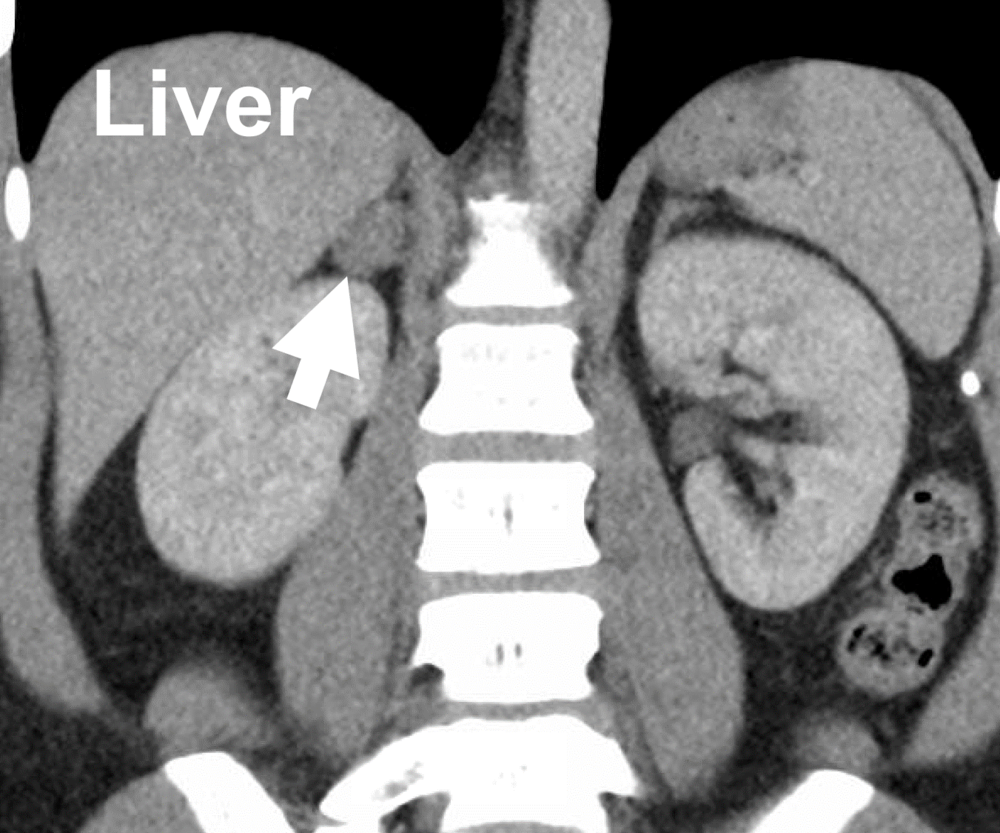

An adrenal adenoma is a benign (non-cancerous) tumor that arises in the cortex (outer layer) of the adrenal gland. These small triangular glands sit atop each kidney and produce hormones critical for stress response, blood pressure, metabolism, salt balance, and more.